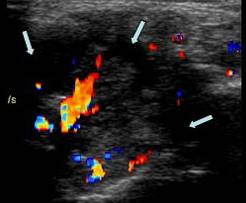

Structura chistica ce disociaza filetele nervoase → cu hiperemie in perinerv →

Pe IRM se evidentiaza hipertrofie nervoasa in T2 si prinde contrast in periferia chistului in T1